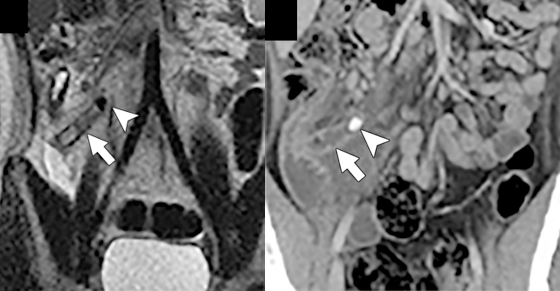

In the same way that NASA’s Apollo program sparked the development of new technologies (many of which were largely realized and appreciated years later) that landed the first humans on the moon, we are witnessing a fundamental transformation in health care operations that will be captured in future history books. Few could have predicted, for example, that CT scans would become an indispensable screening, diagnostic, staging, and management tool during a global pandemic. Providers have harnessed such a wide swath of tools—from laptops, mobile and wearable devices, and video conferencing to artificial intelligence, thermal sensors, and robots—to better serve patients and their loved ones, sustain remote reading and teaching environments, and uphold compliance and safety protocol. We now achieve efficiencies through rapid scanning, recruit new faculty through social media, teach our trainees in cloud-based classrooms, and attend national conferences with just a click—all without ever boarding a plane or even crossing clinical campuses.